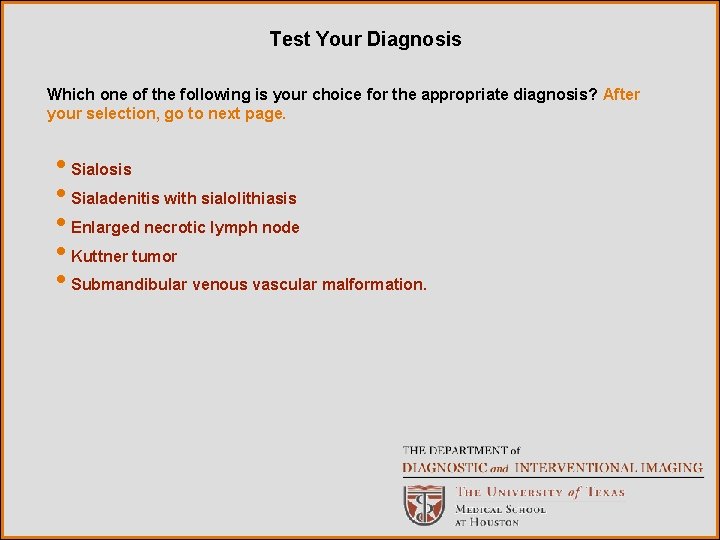

Test Your Diagnosis Which one of the following is your choice for the appropriate diagnosis? After your selection, go to next page. • Sialosis • Sialadenitis with sialolithiasis • Enlarged necrotic lymph node • Kuttner tumor • Submandibular venous vascular malformation.